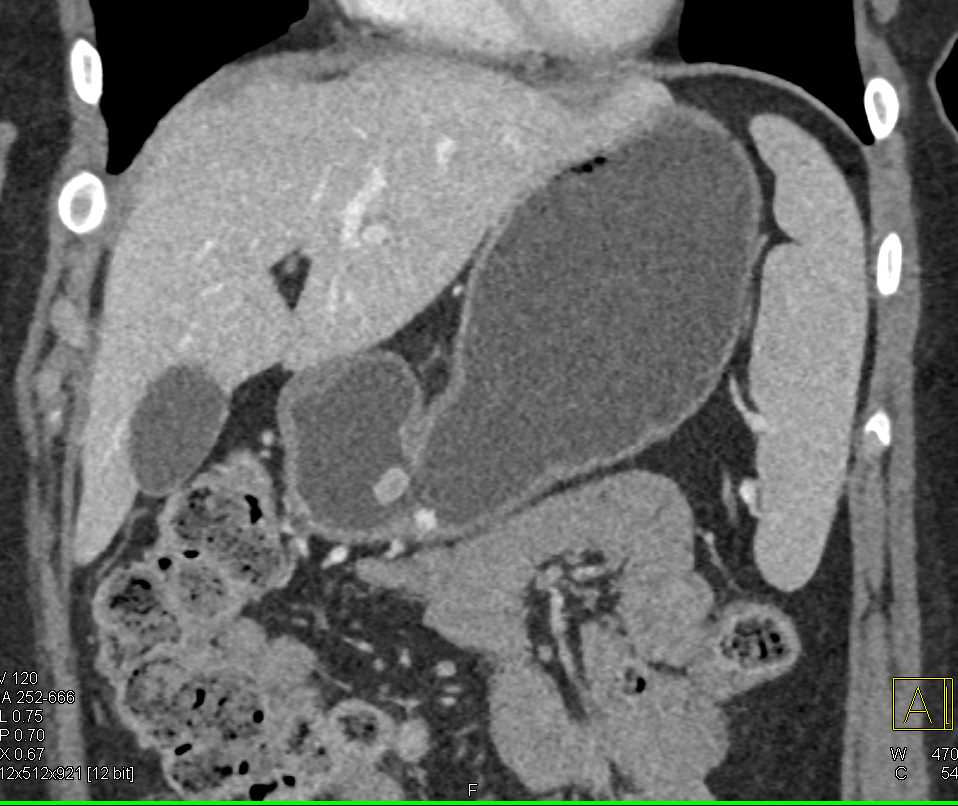

Carcinoid Tumor in the Gastric Antrum